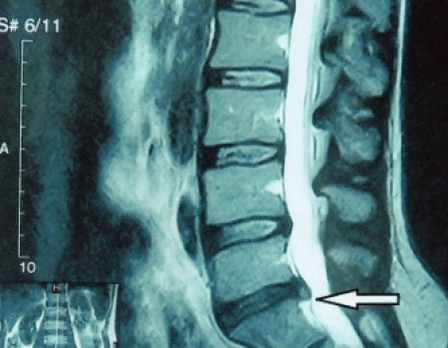

Since discs can only be seen with CT or MRI, magnetic resonance and X-ray computed tomography are indicated to clarify the internal structure of the cartilage and formations such as protrusions and hernias.Thus, with the help of these methods, an accurate diagnosis is made, and the findings of tomography are an indication and even a topical guide for surgical treatment of hernia in the department of neurosurgery.

- if you have a hernia, you must monitor it dynamically, do regular magnetic resonance imaging, avoid increasing its size or carry out modern minimally invasive surgical treatment, because without exception, all conservative methods of treatment for exacerbation of osteochondrosis leave the hernia in place, and remove only temporary symptoms: inflammation, pain, tearing and muscle spasms.

It is recommended that every patient, after the progression of symptoms, in the presence of complications, undergo MRI and consult a neurosurgeon.Modern minimally invasive operations enable the safe removal of rather large hernias, without prolonged hospitalization, without forced lying down for several days, without endangering the quality of life, because they are performed with modern video endoscopic, radio frequency, laser technology or the use of cold plasma.You can vaporize part of the core and reduce the pressure, reducing the risk of developing a hernia.And you can radically eliminate the defect, that is, get rid of it completely.

There is no need to fear hernia surgery;these are no longer the previous types of open surgeries of the 80s and 90s of the last century with muscle dissection, blood loss and subsequent long recovery periods.They are more like a small puncture under X-ray control followed by the use of modern technology.